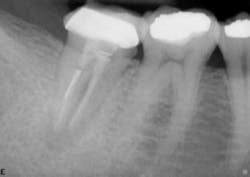

Fig. 2 — Tooth #14 was sensitive to percussion. Endodontic therapy was completed three months prior to the referral. The existing endodontic therapy approximates the root end, but anatomy was clearly missed.

Fig. 2a — Retreatment postoperatively. The canals have been enlarged and a missed MB2 was treated. Shortly after completion of treatment, No. 15 developed symptoms and is in the process of endodontic therapy.Recent research has focused on the long-term survival of endodontic treatment. In a 2004 study, the outcomes of more than one million root canal-treated teeth in more than one million patients was assessed over an eight-year period.4 Using Delta Dental’s national database as a resource, researchers were able to amass an extensive sample size of endodontically treated teeth (both general dentist and specialist). Overall, the study found that the retention rate of root canal-treated teeth was 97% over the eight-year period. Of the teeth with an "untoward event" — namely, a retreatment, apicoectomy, or extraction — the event occurred mostly within a year from the time of original treatment. An analysis of the teeth extracted after endodontic therapy showed that 85% had no full coronal coverage, highlighting the interdependency of successful endodontics and successful prosthetics. Controlling variables such as caries after access and tooth type, it was shown that endodontically treated teeth not crowned after obturation were lost at a 6.0 times greater rate than teeth crowned after obturation.5Previously published articles have sought to compare the success rates of dental implants with the success rates of endodontic procedures, a hard comparison to make because of the vast differences in treatment. One treatment modality depends on halting and reversing periradicular disease, and the other depends on the integration of a prosthetic medical device into native or regenerated tissue (Fig. 3). In a comparison of initial nonsurgical endodontic treatment and single-tooth implants, it was found that restored endodontically treated teeth and single-tooth implant restorations have similar success rates.6 Implants showed a longer average and median time to function and a higher incidence of postoperative complications that required subsequent treatment intervention. Such interventions included peri-implant grafts, treatment of screw loosening, treatment of abutment fractures, and bone augmentation. In a similar study, it was shown that although endodontic therapy and single-tooth implant placement had similar success rates, more maintenance was needed with the dental implants.7